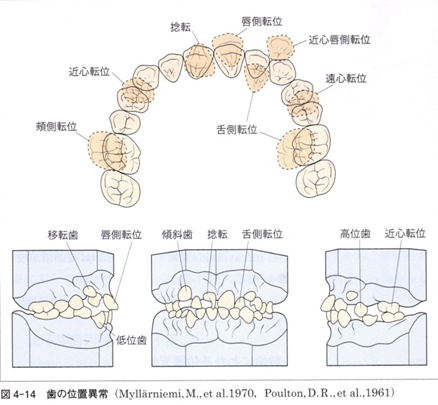

第1,2回では矯正学の最終目標である個性正常咬合を理解してもらいました。

そこでは28本の歯が叢生(歯列不正)なく整然と咬合している状態を、個性正常咬合としていると確認しました。

ここはキー・ポイントとなるところですが、個性正常咬合では少なくとも28本の歯が図の様に咬合している状態を目標としているのです。

また、当然この図の様な歯列の不正は改善されている事は、言うまでもありません。